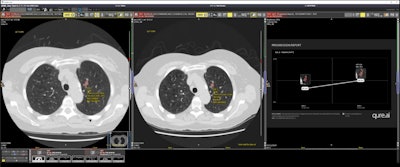

qCT shows nodule development over two timestamps – pulling a prior image and comparing the nodule found across different time periods.Qure.ai